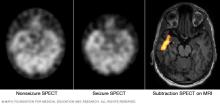

These SPECT images show the blood flow in the brain when there's no seizure activity (left) and during a seizure (middle). The subtraction SPECT coregistered to MRI (right) helps pinpoint the area of seizure activity by overlapping the SPECT results with brain MRI results.

• Single-photon emission computerized tomography (SPECT). A SPECT test uses a small amount of low-dose radioactive material that's injected into a vein. The test creates a detailed, 3D map of the blood flow activity in your brain that happens during a seizure. You may have a form of a SPECT test called subtraction ictal SPECT coregistered to magnetic resonance imaging, also called SISCOM. This can compare blood flow during a seizure to blood flow in between seizures.